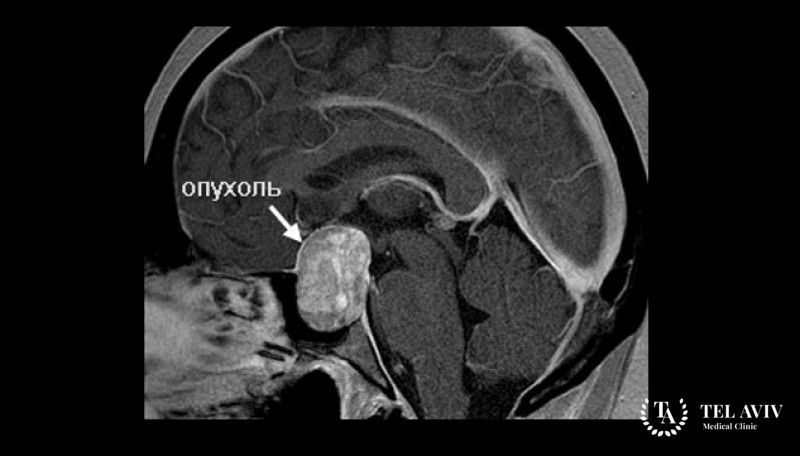

Аденокарциномы относят к категории злокачественных новообразований, поражающих различные органы человека. В основе формирования патологии – железистый эпителий. Заболевание встречается редко. Оно поражает железу внутренней секреции – гипофиз. От функциональности гипофиза зависит гормональный фон организма, производительность гормонов. При наличии сбоев в работе гипофиза происходит нарушение работы всего организма. Велика вероятность бесконтрольного набора массы тела, резкого похудения. Гипофиз регулирует работу репродуктивной функции.

- Злокачественные новообразования, прорастающие из гормонально активной аденомы, расположенной в зоне гипофиза;

- Опухоли, прорастающие из не активной аденомы, локализирующейся в области железы.